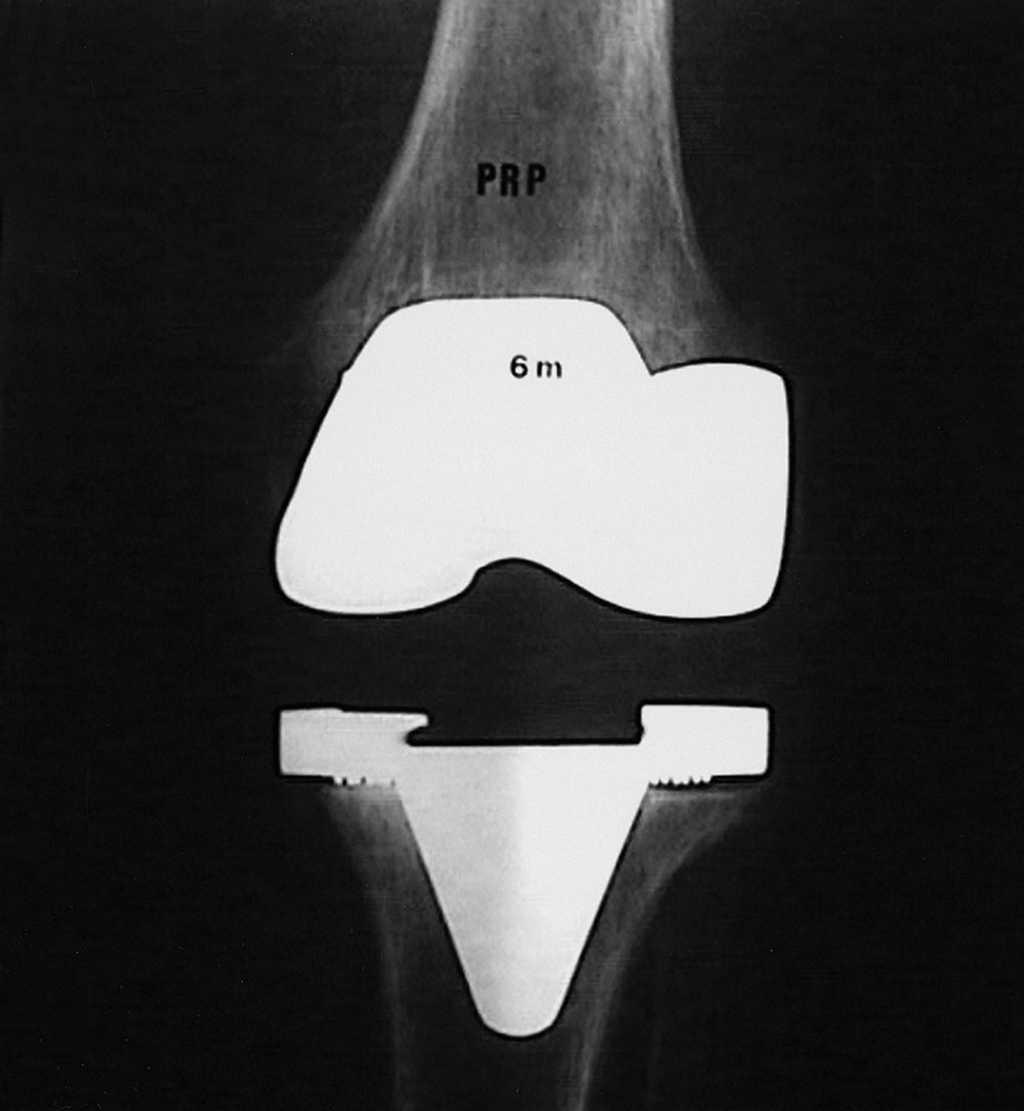

De los 33 pacientes controlados, cinco padecieron un procedimiento de revisión. Un paciente de 75 años precisó de una artrodesis para resolver una infección de la prótesis dos años después de haber sido implantada. Otro requirió liberación del alerón externo por cuadro de dolor en cara anterior de la rodilla y malposición rotuliana 16 meses después de ser intervenido. Por problemas relacionados con el implante, se revisaron tres pacientes. En un caso, una inestabilidad grave ligamentosa ya presente en el preoperatorio, se trató mediante un recambio del platillo tibial por otro mayor a los dos años del implante en un intento por constreñir la articulación. Al no alcanzar el objetivo deseado se recambió por una prótesis constreñida (rotatoria de LINK ® ) dos años después. En los dos casos restantes, se detectó un aflojamiento aséptico del componente tibial a los seis meses (fig. 1) y dos años tras el implante. Como procedimiento de rescate también se usó una prótesis constreñida.

Figura 1. Radiografía anteroposterior de una prótesis con radiolucen cias sugestivas de aflojamiento del componente tibial, seis meses des pués de ser implantada.